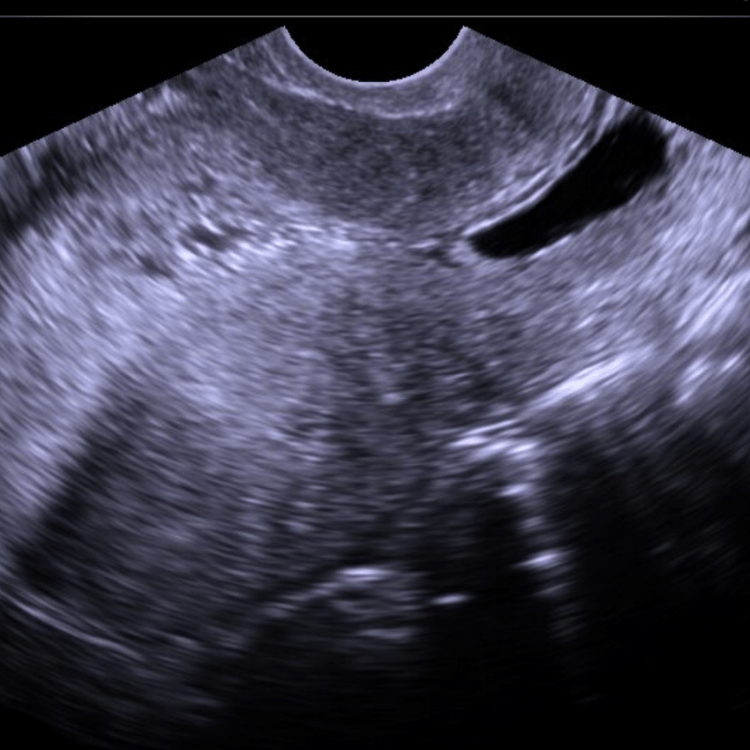

Actualmente trabajo como profesionista independiente. Realizo estudios de ultrasonido de todo tipo: abdominal, renal, hepatobiliar, ginecológico, prostático, tiroideo, inguinal, escrotal, así como estudios de arterias y venas (Doopler color y espectral) en brazos, piernas y cualquier otro órgano del cuerpo. En caso de indicación médica puedo realizar biopsias del cuello (tiroides y ganglios), abdomen (hígado, riñón) o próstata, así como extraer líquido acumulado en la pleura (membrana que recubre los pulmones) y en el abdomen, entre otros.